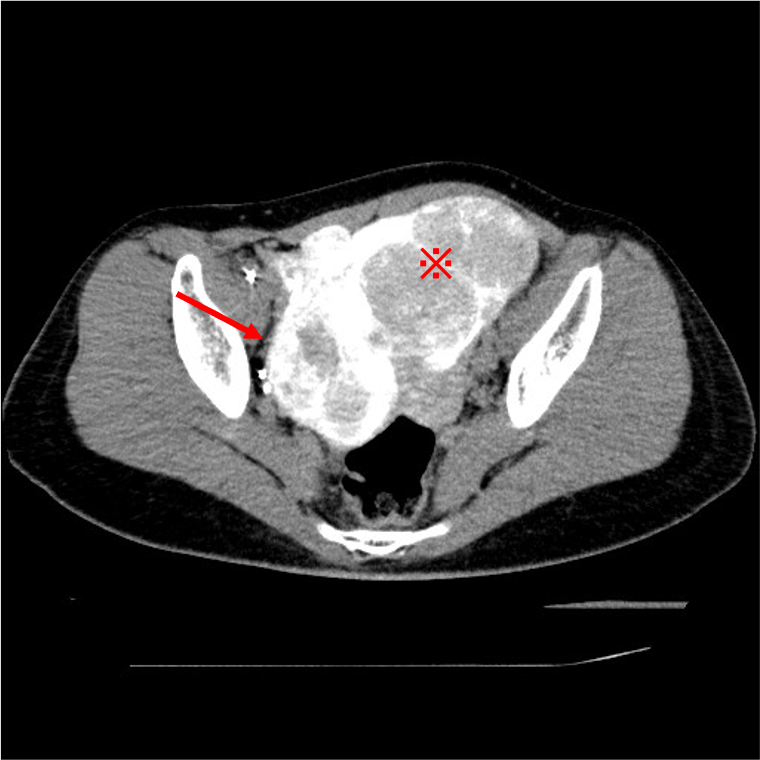

UAEの合併症には下腹部痛、術後感染、筋腫の子宮内腔脱落の他に、卵巣機能不全(45歳未満:0-3%、45歳以上:20-40%1))、非標的塞栓などがある。そのため、UAEを施行する際には、術前にMRIやCTにより子宮筋腫の局在や血管走行を確認してから治療を行う必要がある。我々は血管造影時に選択的子宮動脈造影と血管造影下CT (CT Uterine Arteriography :CTUA)を施行することにより、卵巣の濃染の有無や、拡張した子宮卵巣動脈吻合の有無、膣や子宮頸部の濃染の有無を確認し、UAEを施行している2)。Type1BやType3の子宮卵巣動脈吻合3)がみられた場合、UAEにより塞栓物質が子宮卵巣動脈吻合に流入し、卵巣機能不全に陥る可能性がある。そのためCTUAにより子宮卵巣吻合の分岐を確認し、子宮卵巣吻合のType分類を行い、子宮卵巣吻合が太く、卵巣への血流が豊富な場合(Type1B,Type3)には、子宮卵巣動脈吻合のコイル塞栓を施行している。CTUAを施行することにより、塞栓物質の非標的塞栓や子宮卵巣動脈吻合への塞栓物質の流入を防ぎ、安全にUAEが可能である。

使用造影剤:5倍希釈造影剤、注入速度:1.5mL/sec、Scan時間:撮像範囲による(本症例では約4秒)、Scan delay時間:9秒、造影剤の注入量:(Scan時間+Scan delay9秒)×1.5mL/sec。

本症例ではイオプロミド300注を使用し、一度のCTUAでの造影剤使用量は約4.0mL相当である。

子宮筋腫の濃染をみたいため、CTUA中は造影剤を注入している。Scan時間は子宮サイズに影響を受ける。

造影剤の逆流により、子宮頸部が造影されたり、Type3の子宮卵巣動脈吻合と誤認してしまうのを防ぐため、造影剤を強く注入しすぎないように注意し、撮像前にはAngio造影を見て、注入速度や注入量の微調整を行っている。